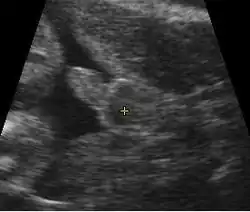

Première échographie

L'échographie au premier trimestre de la grossesse permet :

- de s'assurer de la vitalité de la grossesse par la présence d'un embryon présentant une activité cardiaque ;

- d'affirmer le caractère unique de l'embryon ou multiple. S'il existe deux embryons, il s'agit d'une grossesse gémellaire. En cas de grossesse gémellaire il est important pour le suivi correct des grossesses de savoir s'il existe un placenta ou deux placentas qui alimentent l'embryon. On parle dans ce cas de grossesse monochoriale s'il existe un placenta (absence de signe du lambda) et de grossesse bichoriale s'il existe deux placentas (signe du lambda présent) ;

- de dater le début de grossesse en mesurant la longueur de l'embryon (longueur craniocaudale), avec une précision de l'ordre de 7 jours[27] ;

- d'évaluer le risque que l'embryon soit porteur d'anomalie chromosomique comme la trisomie 21 par mesure de la clarté nucale ;

- de voir certaines malformations ou pathologies à expression échographique précoce.